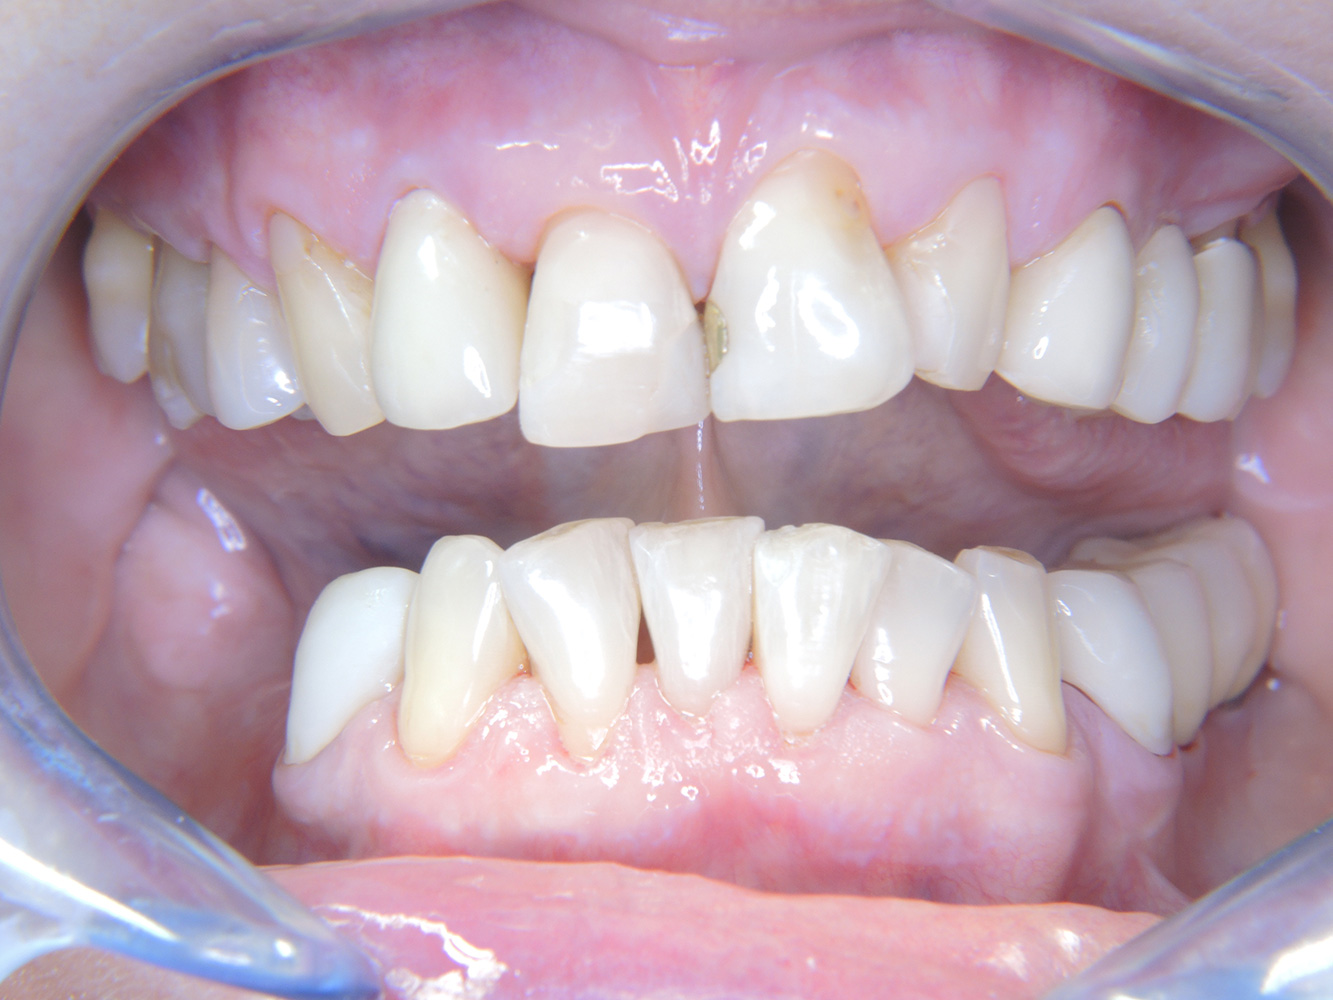

Die 68-jährige Patientin hat keine zahnmedizinisch relevanten allgemeingesundheitlichen Vorerkrankungen oder Medikation, auch aus dem Lebensstil ergibt sich kein besonderes Risiko. Die Patientin hat zwei Implantate (3. Quadrant, seit fünf Jahren) sowie eine parodontale Vorerkrankung (Parodontitis Stadium IV, Grad B) mit Zahnverlust. Derzeit zeigen sich stabile parodontale Verhältnisse, jedoch erhöht Parodontitis maßgeblich die biologischen Komplikationen bei Implantationen und es droht der Implantatverlust (21).

Da die Patientin keine besonderen Risikofaktoren mit spezifischen zahnmedizinischen Auswirkungen hat, ist der aus der Mundgesundheit ermittelte Bedarf maßgebend. Hier ist einmal jährlich ein ausführlicher Parodontalstatus empfohlen. So kann rechtzeitig auf eine mögliche Progression der parodontalen Vorerkrankung oder die Entstehung einer Periimplantitis reagiert werden.

Aufgrund der Implantatsituation mit parodontaler Vorerkrankung hat die Patientin ein Entstehungsrisiko für eine Periimplantitis – empfohlen wird eine Wiedervorstellung im Intervall von drei bis vier Monaten.